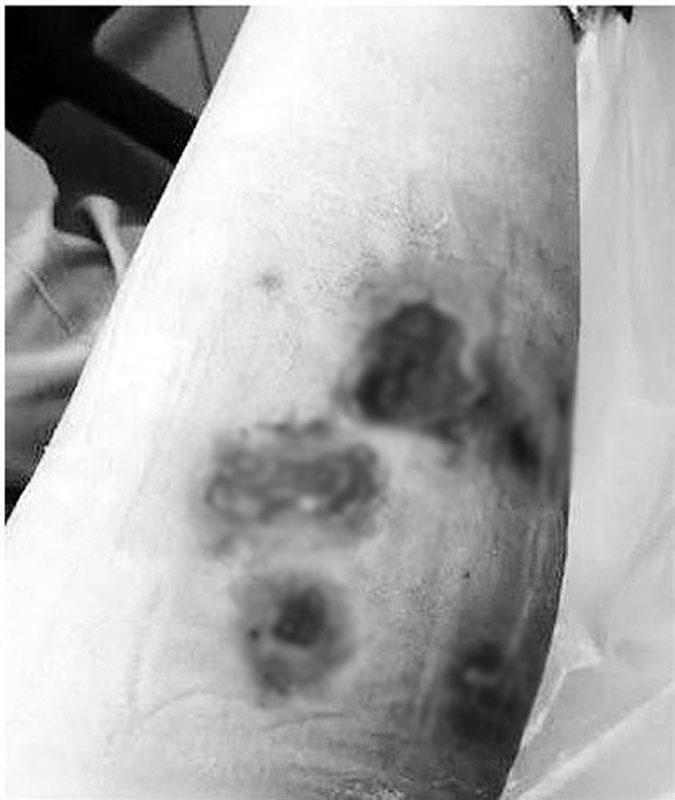

Sau một tuần, trình trạng được cải thiện nhưng nhanh chóng tái phát trở lại. Lúc này, điều trị bằng kháng sinh không có kết quả, hai chân của Tiểu Lý xuất hiện vết loét, mủ, vùng da và mạch máu xung quanh chuyển sang màu đỏ tím.

Hình ảnh vết thương trên chân của Tiểu Lý

Lúc này, Tiểu Lý đã đến bệnh viện để điều trị. Tuy nhiên khi nhập viện, các bác sĩ không tìm được nguyên nhân khiến chân Tiểu Lý bị nhiễm trùng, hoại tử. Sau gần một tháng, các chuyên gia mới xác định trực khuẩn mà cô gái trẻ nhiễm phải, đó là Mycobacteria không điển hình. Chúng có thể gây nhiễm trùng da và phổi ở những bệnh nhân có hệ miễn dịch thấp.